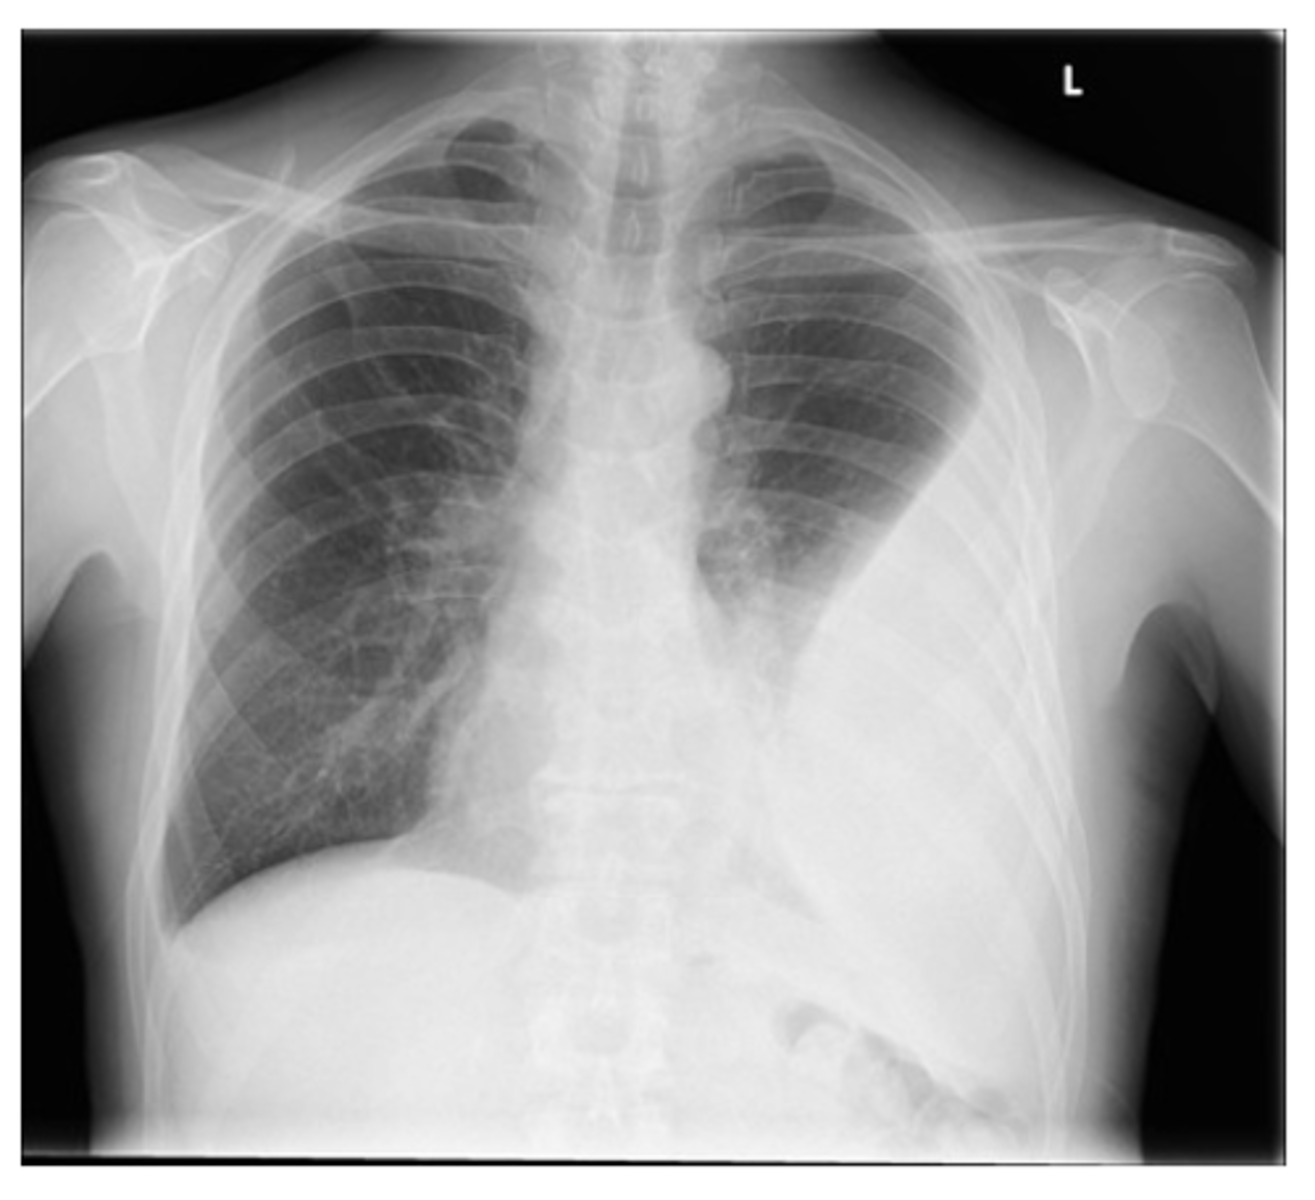

Bronchiectasis

-tram lines

Dx. What is this finding?

<p>Dx. What is this finding?</p>